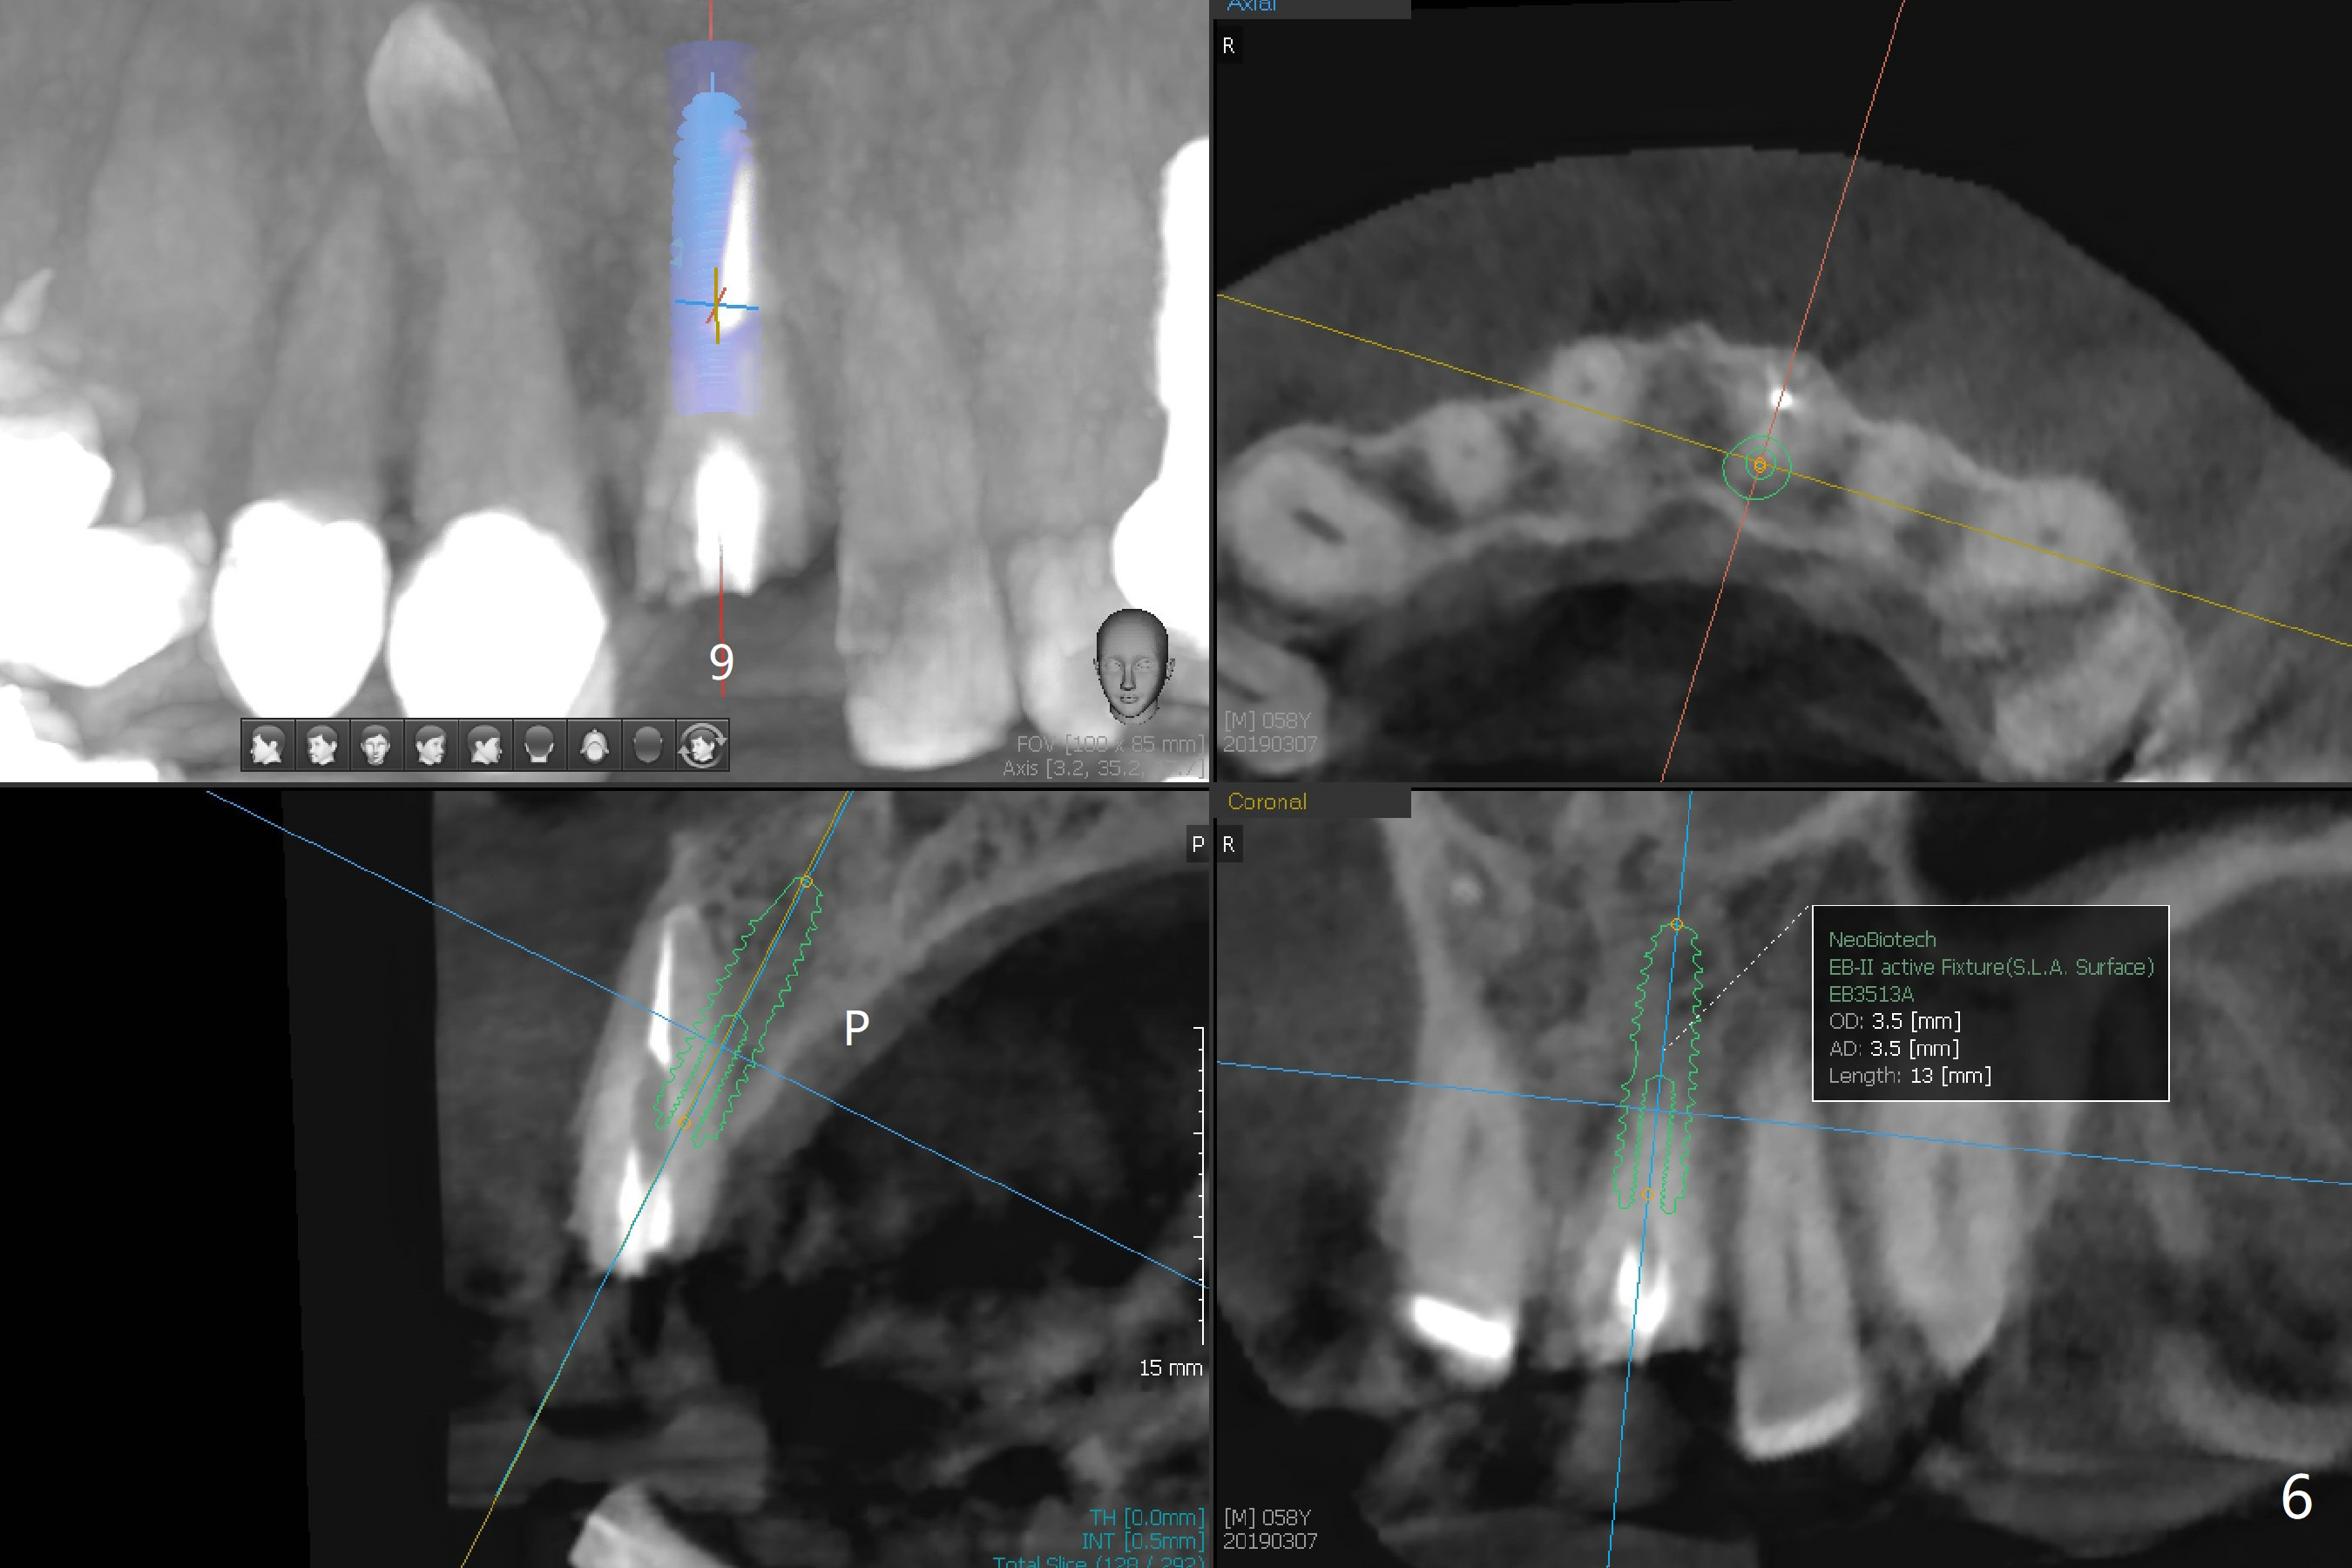

A 58-year-old man fractures the tooth #9 equigingival (Fig.1) and fiber post (Fig.2,3 *). The marginal gingiva is erythematous and edematous (Fig.1 *), suggesting biologic width violation. Redo crown would aggravate the issue. In addition, the mesiobuccal root of the tooth #14 has vertical fracture (Fig.4,5), evidence of heavy mastication. In fact the tooth #13 was also fractured apparently due to heavy occlusion before extraction. It is the best to extract the tooth #9 for implant (Fig.6), or tissue-level (3.5x14 or 17 mm).